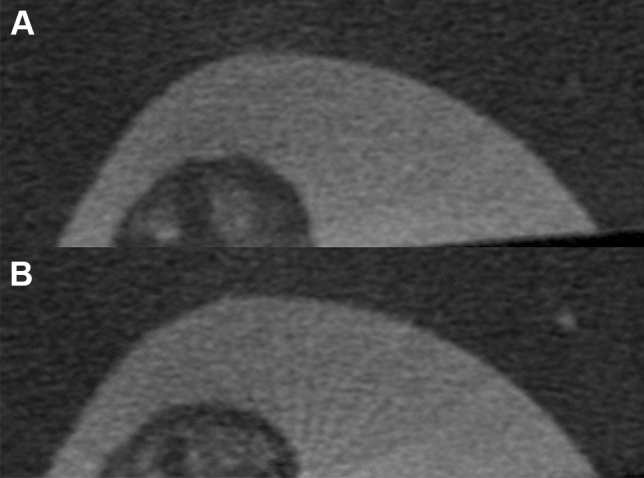

Fig. 4 .

3D reconstructed µCT images of the ROI area shown in Fig. 1E using the two energy sources studied. A 50 kV image shows a vaguer appearance of the dentin structures and a less defined architecture. B 100 kV image shows a more defined appearance of the dentin structures and trabeculation

Calibration comparisons between the 2 rods HA phantom using 50 kV and 100 kV are shown in Table 1. The mean of DMD when using 50 kV for groups 1, 2, 3, 4, 5, and 6 was 4.05, 4.39, 5.79, 4.14, 4.89, and 5.57, respectively. There was no significant difference between Groups 1 and 4, Groups 2 and 5, and Groups 3 and 6. The mean of DMD when using 100 kV for groups 1, 2, 3, 4, 5, and 6 was 5.92, 5.45, 7.69, 6.11, 5.62, and 6.48, respectively. A non-significant difference was found between groups 1 and 4, groups 2 and 5, and groups 3 and 6. μCT operating at 100 kV was found to grant more accurate measurement of DMD in all tooth groups tested (Tables 2, 3, 4). In molars, it was statistically significant at the CEJ and apical levels (Table 2). At the mid-root level, 100 kV yielded higher accuracy than 50 kV; however, the difference was not statistically significant. In premolars, 100 kV yielded significantly higher DMD accuracy than 50 kV in all levels of the root (Table 3). In anterior teeth, 100 kV was also significantly more accurate in all levels of the root (Table 4). 3D reconstructed 50 kV µCT images showed a slightly vague radiopaque dentinal structure, and less-defined dentin architecture (Fig. 4). 3D reconstructed 100 kV µCT images produced a more defined dentin structure and trabeculation (Fig. 4).